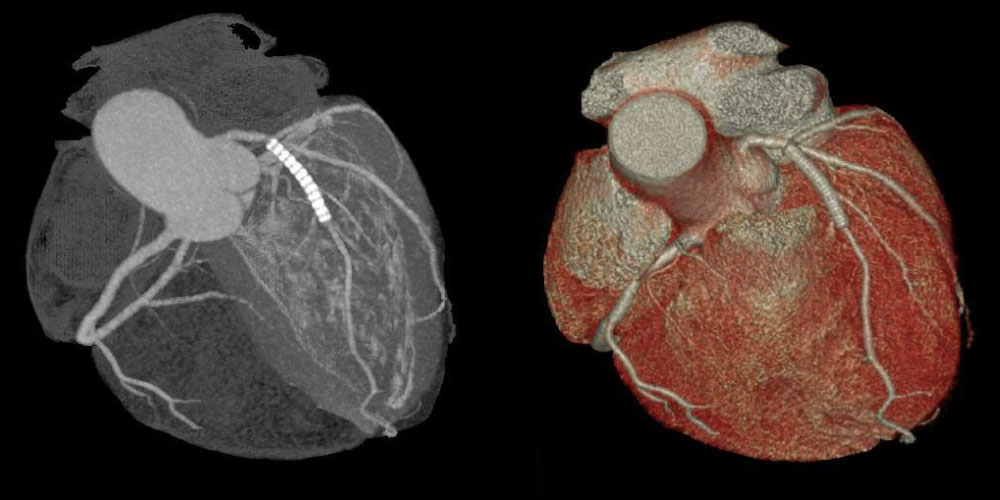

心臓冠動脈造影

心臓には冠動脈と呼ばれる血管があり、この冠動脈の状態を検査する方法の一つに心臓CT検査があります。

冠動脈は微細かつとどまることなく常に動き続けており、冠動脈を静止画像として画像化することは非常に困難なことですが、当院の最新型80列CT装置では、高速での撮影かつ高精細な画像の撮影が可能なため、心臓においても他の動きのある臓器同様に動きやボケのない高画質な画像提供が可能です。

冠動脈が動脈硬化によって狭窄や閉塞を起こし、狭心症や心筋梗塞を発症します。

冠動脈血管の狭窄を起こす原因となる石灰化の有無などが評価ができ、血管の狭窄がある場合その狭窄の度合いも把握できます。